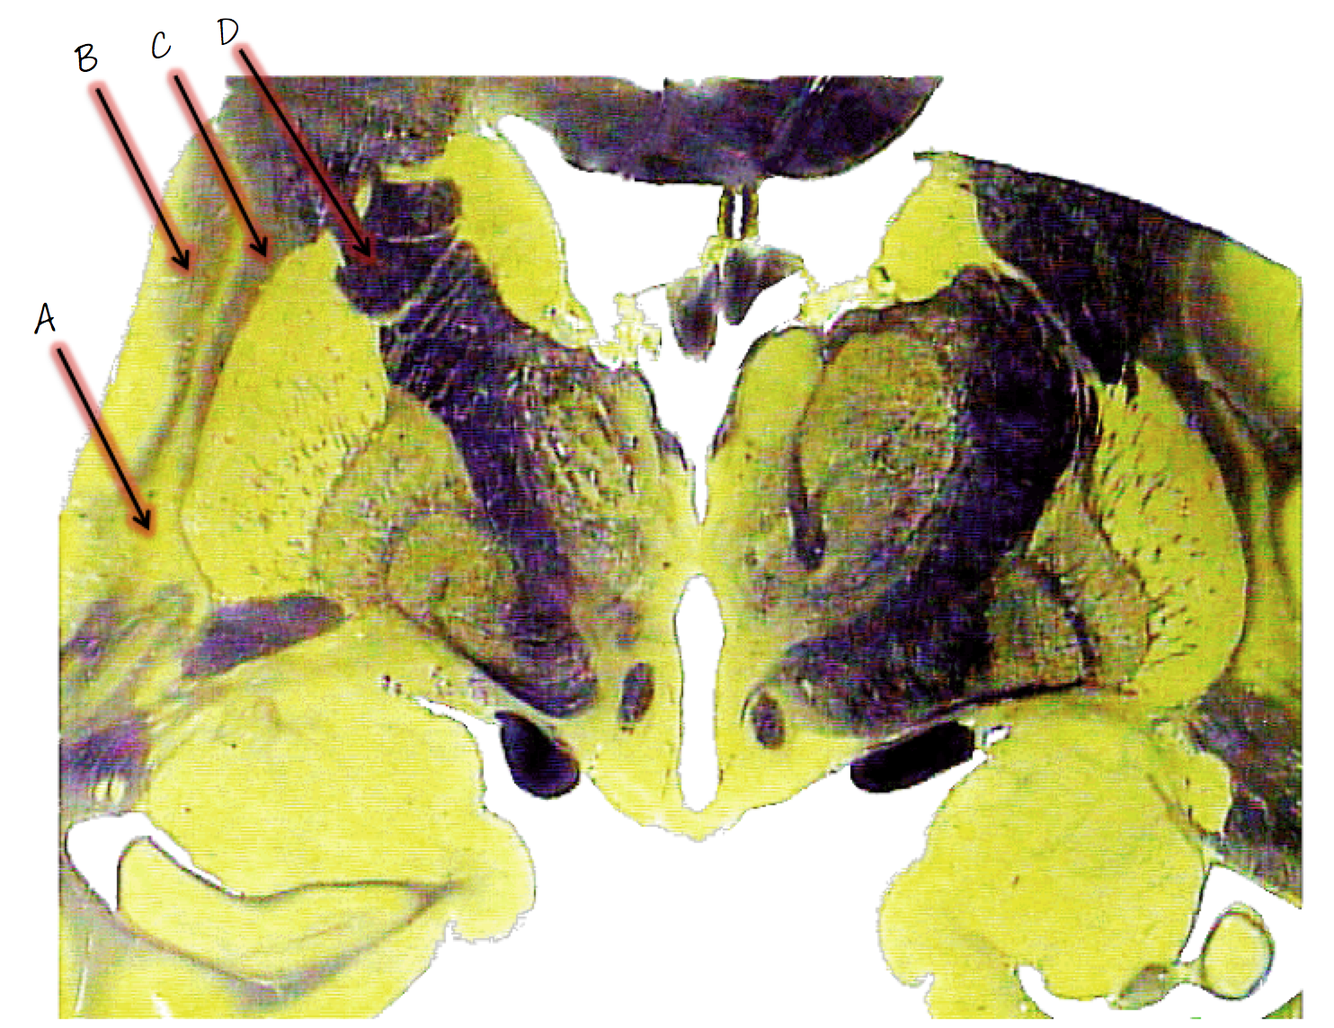

A; red nucleus

B; ventral tegmental area

C; interpeduncular fossa

D; fibers of the oculomotor nerve (CNIII)

E; substantia nigra

F; crus cerebri (crebral peduncle)